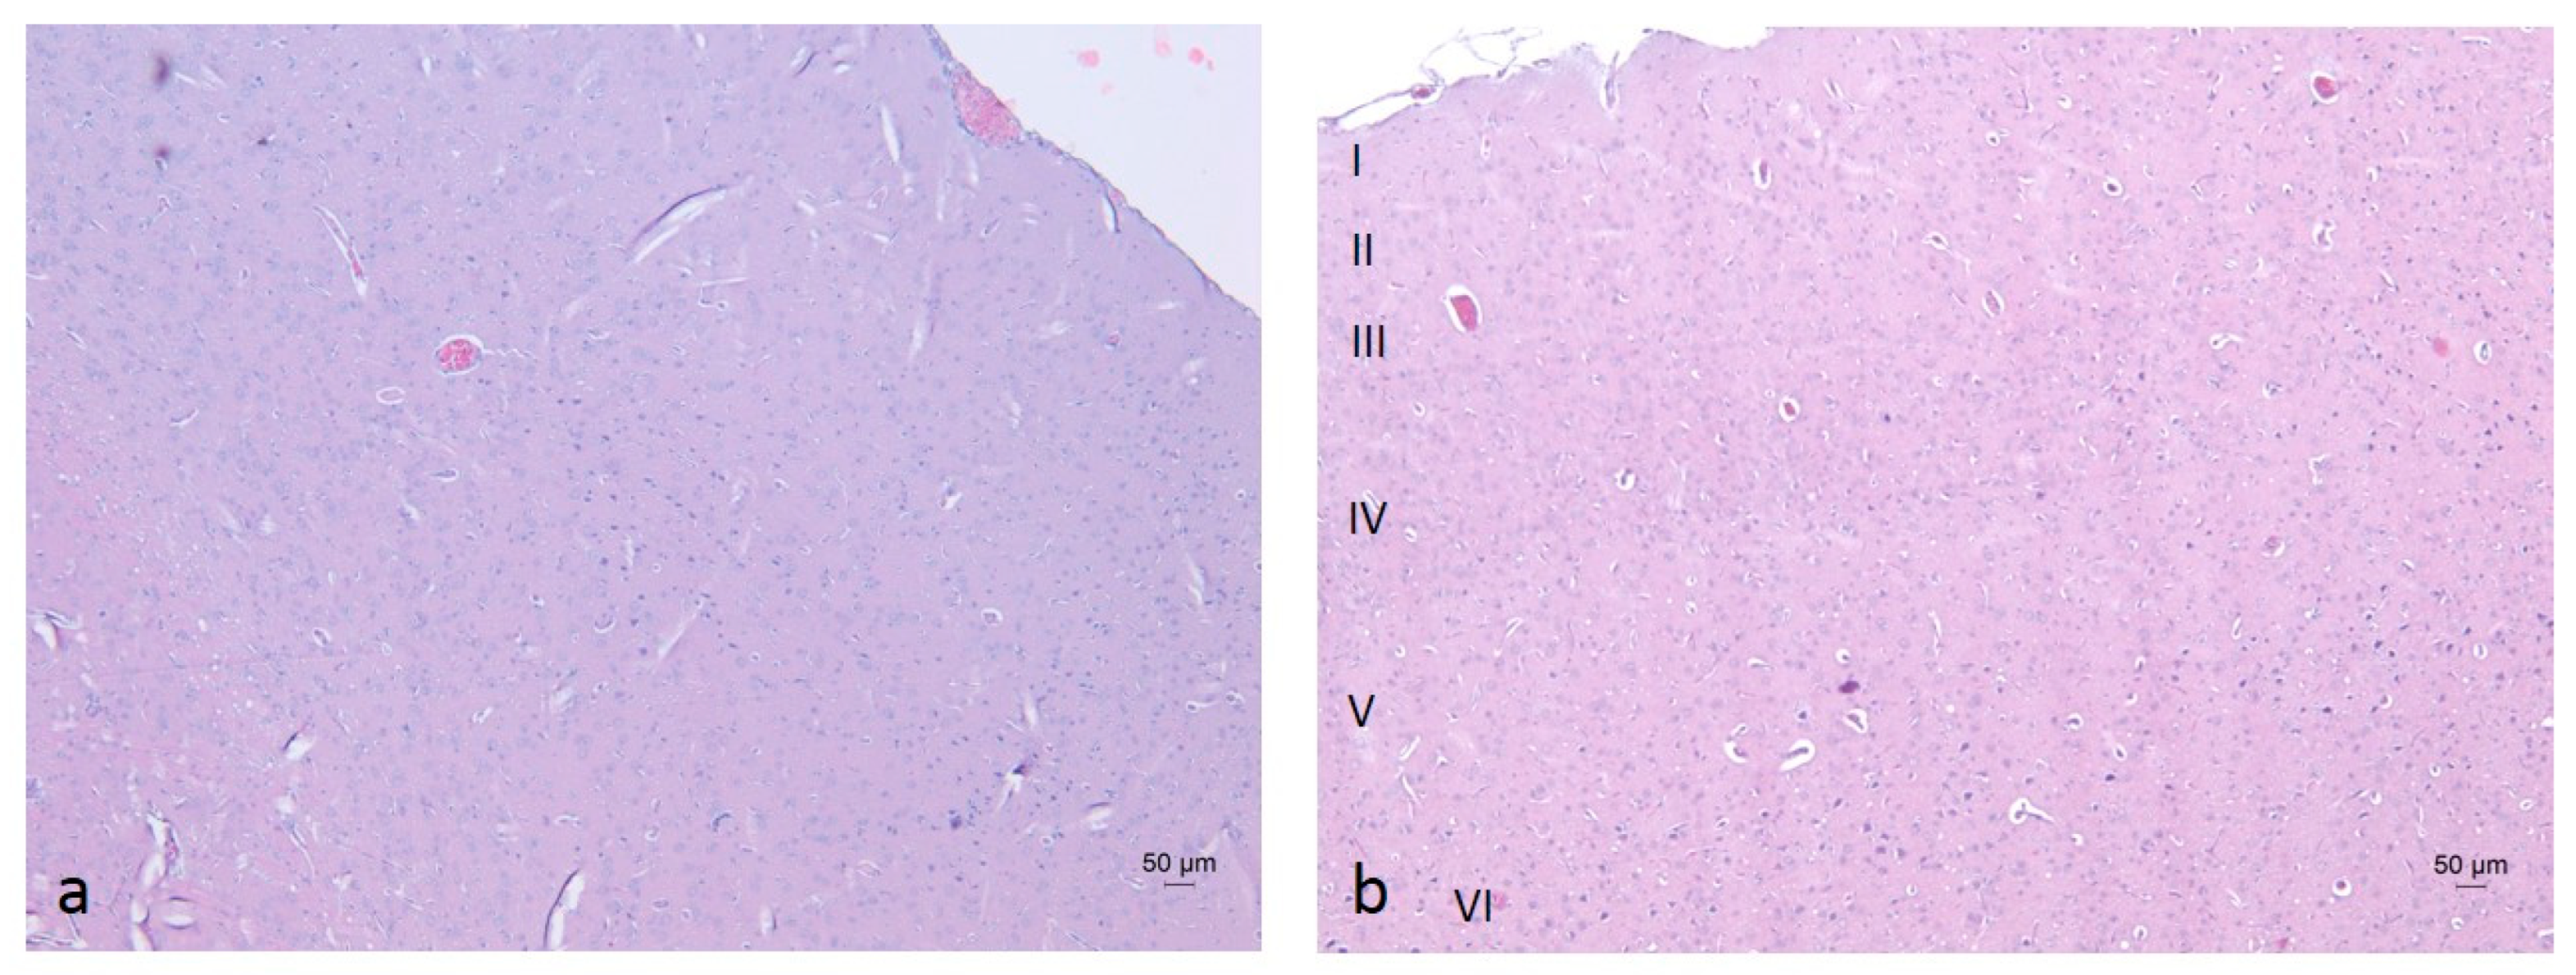

In the cerebral cortex (neocortex), the typical vertical arrangement of cortical neurons and the layered organization of glial cells were observed. In rodents, this region represents an isocortical (eulaminate) area characterized by six well-developed layers, including the granular layer IV (Figure 6 and Figure 7) [70,71]. Vascularization appeared unaffected by the daily oral intake of the ethanol–tap water solution (20%, v/v) at the administered dosage.

Figure 6.

Cerebral cortex of rats from the W-S group (a), E-M group (b), E-R group (c), E-A group (d), and E-S group (e). Staining: Hematoxylin and Eosin (H&E).

Figure 7.

Neocortex of rats from the W-S group (a) and E-S group 4 (b). Cortical layers: I—Molecular layer (lamina molecularis), II—External granular layer (lamina granularis externa), III—External pyramidal layer (lamina pyramidalis externa), IV—Internal granular layer (lamina granularis interna), V—Internal pyramidal (or ganglionic) layer (lamina pyramidalis interna), VI—Multiform layer (lamina multiformis). Staining: H&E.